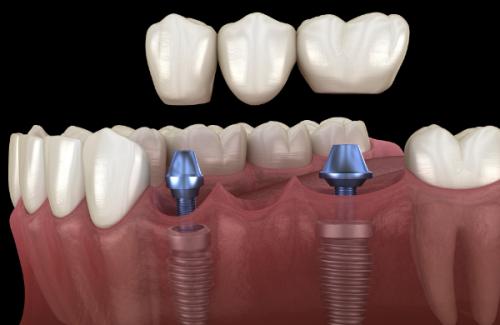

修复阶段:当骨结合完成后,就进入了修复阶段,这个阶段主要是制作和安装牙冠。一般来说,需要2 - 4周的时间。不过对于一些复杂病例,可能需要多次调改咬合关系,这样花费的时间就会更长。就像给房子装修一样,要把每一个细节都调整好,才能让种植牙使用起来更舒适。